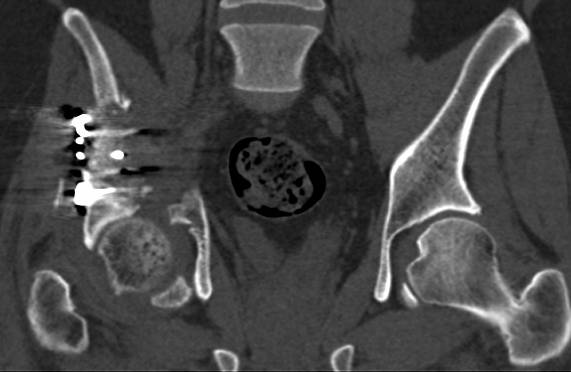

[Ortho] перелом правой половины таза

высылаю дополнительно  сканы.